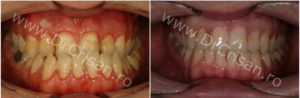

Dupa alte 6 luni de tratament ortodontic … IATA REZULTATUL FINAL. Fotografie frontala Inainte/Dupa

Durata totala de tratament combinat – 16 luni.